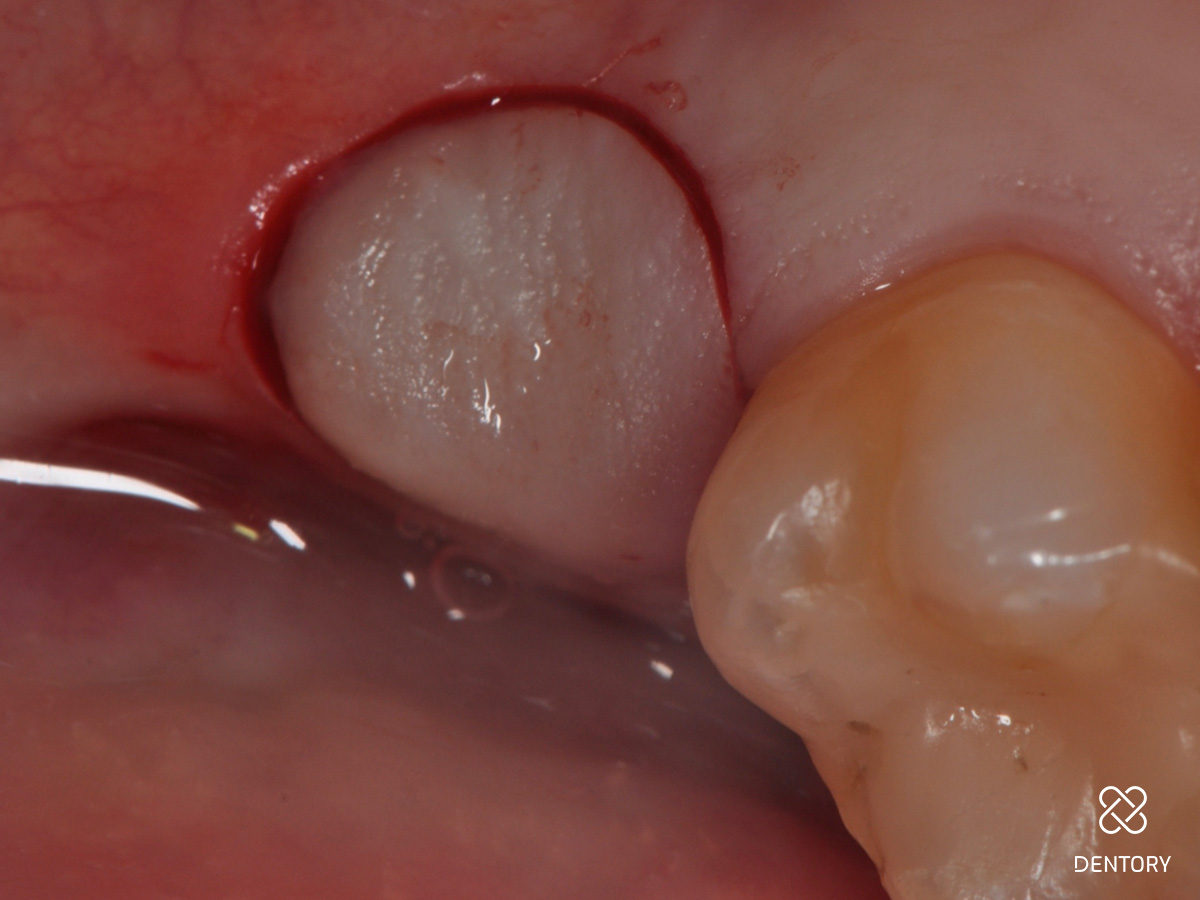

Abbildung 9

Das Transplantat sollte im Durchmesser etwa 1mm breiter als die Extraktionsalveole sein

Abbildung 10

Aus der Tuberregion wird nun distopalatinal des zweiten Molaren in einer Dicke von etwa 4 mm mit einer maschinellen Gewebestanze ein freies Gingivatransplantat entnommen.